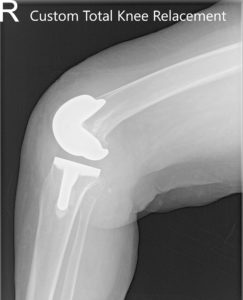

IMPLANTES UTILIZADOS: Personalizado fémur y tibia bilateralmente, con polietileno de 10 mm bilateralmente. Rótula derecha 29 mm x 6 mm y rótula izquierda 32 mm x 6 mm.

Radiografía postoperatoria que muestra AP y vistas laterales de la articulación de la rodilla derecha e izquierda.